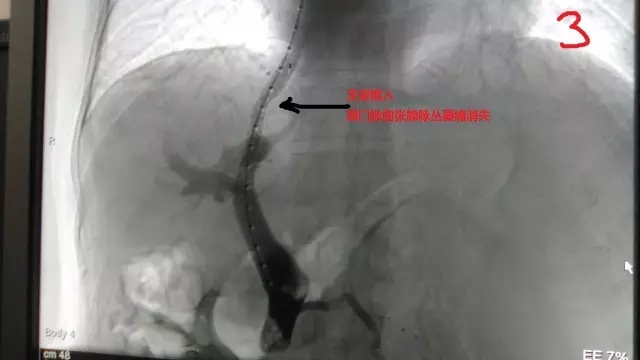

患者入住消化內科,經充分術前準備后,于2017年5月8日介入科為患者進行了門脈高壓介入門體分流(TIPS)支架手術,肝實質支架再建搭橋通道通暢滿意,門脈水柱壓力當即由48cm下降為33cm,胃底食道曲張靜脈萎縮消失。遠期療效更可樂觀期待?,F術后恢復順利,患者癥狀改善滿意稱謝,充分體現了介入手術微創(chuàng)、高效、可控的優(yōu)勢。

術后胃底食道曲張靜脈萎縮消失